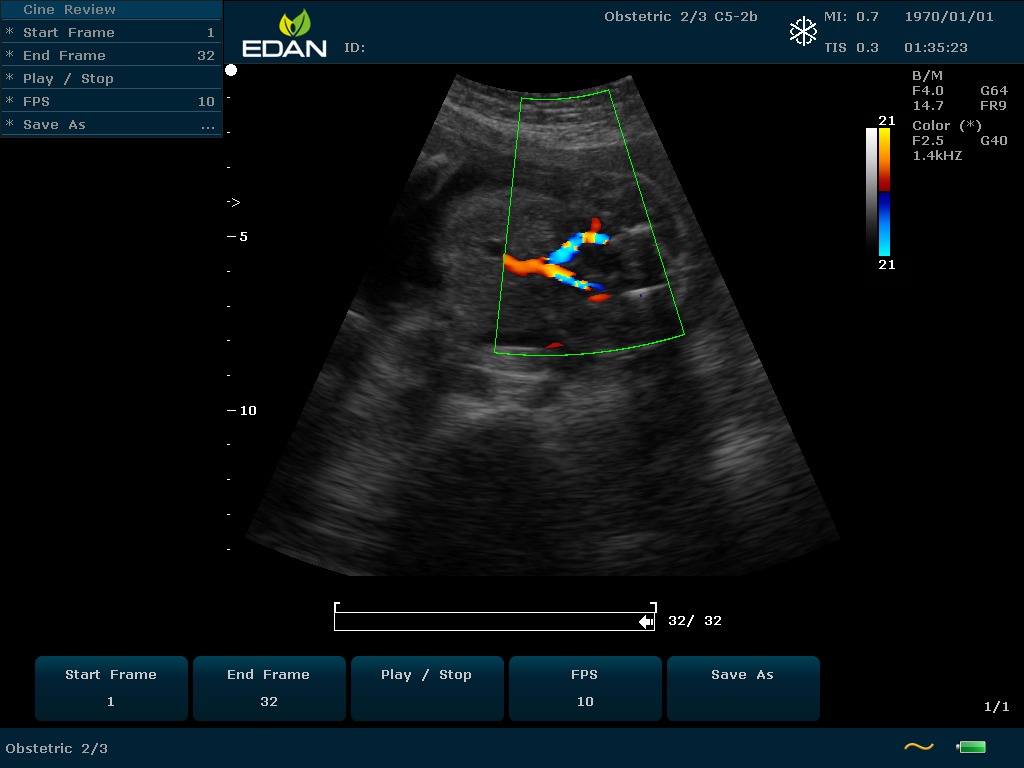

Особенность U60 Edan — расширенное применение. Ультразвуковой аппарат рекомендован для абдоминальных исследований, гинекологии и акушерства, кардиологии, педиатрии, урологии, изучения малых органов, сосудов. Для U60 Edan используются конвексные, линейные, фазированные и внутриполостные датчики.

Передовые технологии позволяют повысить качество визуализации в несколько раз. УЗИ-аппарат U60 Edan отличается возможностью быстрой настройки визуализации. Специальные функции позволяют моментально отображать данные за счет быстрой оптимизации параметров. Режимы визуализации: B-mode, M-mode, Color Doppler, Power Doppler Imaging, Pulsed Wave Doppler, Continuous Doppler.

• Цветовое Допплеровское картирование